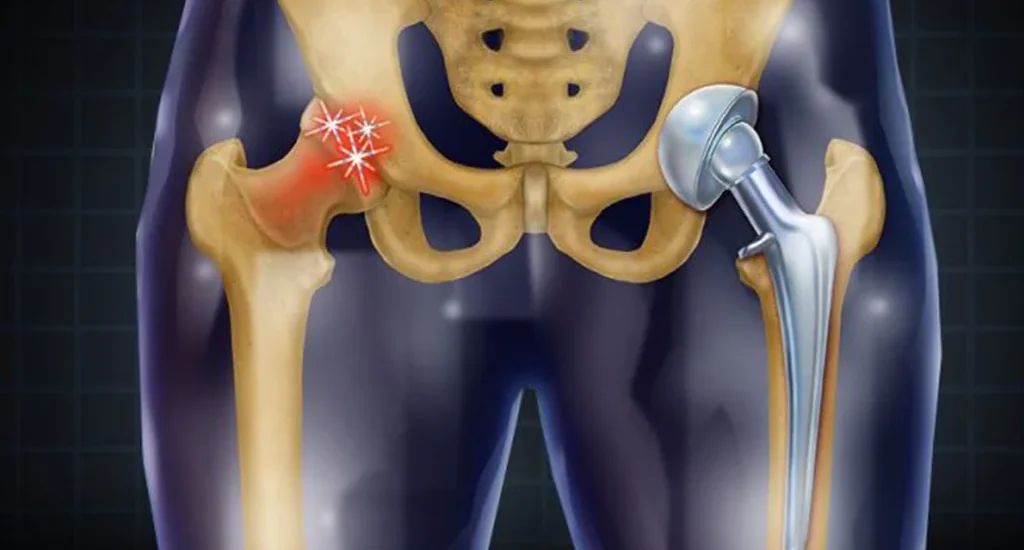

SYNERGY BONE AND SKIN CLINIC Orthopaedic and dermatology clinic in the heart of Vaishali Nagar. We Specialize in Sports injuries and Trauma, bone and joint pains, joint arthritis and replacement surgeries. The only clinic in Rajasthan that specialises in Geriatric ( old age ) orthopaedics. All dermatological and cosmetic treatments and procedures are done here with precision and perfection. Hair Transplant surgery, Laser treatments, Chemical peels, Tattoo removal, microsurgery, De-tanning, anti-aging, and rejuvenation therapies are done here. All the treatments are accurate, clinically motivated, and incorporate the latest therapies. We follow international protocols and all treatments are customized to meet patient's needs and lifestyle.